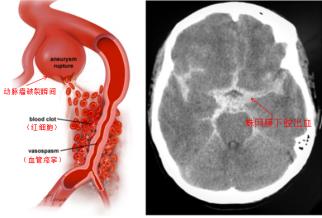

顱內(nèi)動脈瘤并非真正的腫瘤,而是顱內(nèi)動脈壁局部的異常膨出,就像血管壁上鼓起的一個“小氣球” 或“小泡”。這個“小泡” 的壁通常很薄,隨著血流不斷沖擊,它會逐漸變大,當壓力超過壁的承受極限時,就會發(fā)生破裂,引發(fā)蛛網(wǎng)膜下腔出血。這種出血來勢洶洶,約30%的患者會在首次破裂后便會直接失去生命,即使僥幸存活,也可能留下偏癱、失語、認知障礙等嚴重后遺癥,給個人和家庭帶來沉重打擊。